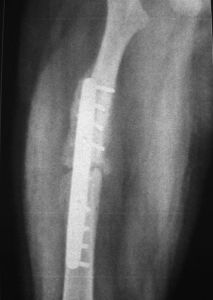

95°角鋼板優點和DCS相仿可以防止膝內外翻,抗鏇轉、抗剪力,但它不能使髁間加壓、鎖固,對髁部粉碎性骨折,不易解剖復位。

股骨髁支持鋼板外形與股骨遠端外側形態和生理弧度一致、鋼板遠端支持部可呈環形支持股骨外髁、可擰入多枚松質骨螺釘,從而最大限度固定遠側髁部骨塊,操作簡單、特別適用於股骨髁部粉碎性骨折,問題是穿過遠端孔的螺絲釘與鋼板之間無固定系統,常產生對側骨折壓縮,並發膝內翻或肢體鏇轉畸形。若對側再加用支持鋼板,將增大患者創傷,手術時間延長等弊端 。

DCS具有抗彎、抗扭曲、抗剪力及抗鏇轉作用,能使髁間骨折塊加壓、有良好的力學穩定性,固定可靠、牢固堅強,有利於關節早期活動。DCS為95°釘板結合,符合股骨遠端的解剖結構,適用於股骨髁上、髁間骨折、操作時只需在兩個方向精確安裝,操作簡單、鋼板易於與骨幹軸線一致,便於復位。採用DCS系統固定時內固定物不需要敲擊,只需沿導針滑動,從而保證內植物前進方向。但DCS也有它的局限性,對老年骨質疏鬆症嚴重的應慎用。在動力加壓螺釘和鋼板結合部突出,同時不適用於髁部粉碎性骨折。

綜上所述DCS是治療股骨髁上骨折的手術方法中,固定最穩定、療效較可靠的動力髁固定系統,如能正確掌握適應證,術中準確操作、可以取得良好的治療效果。